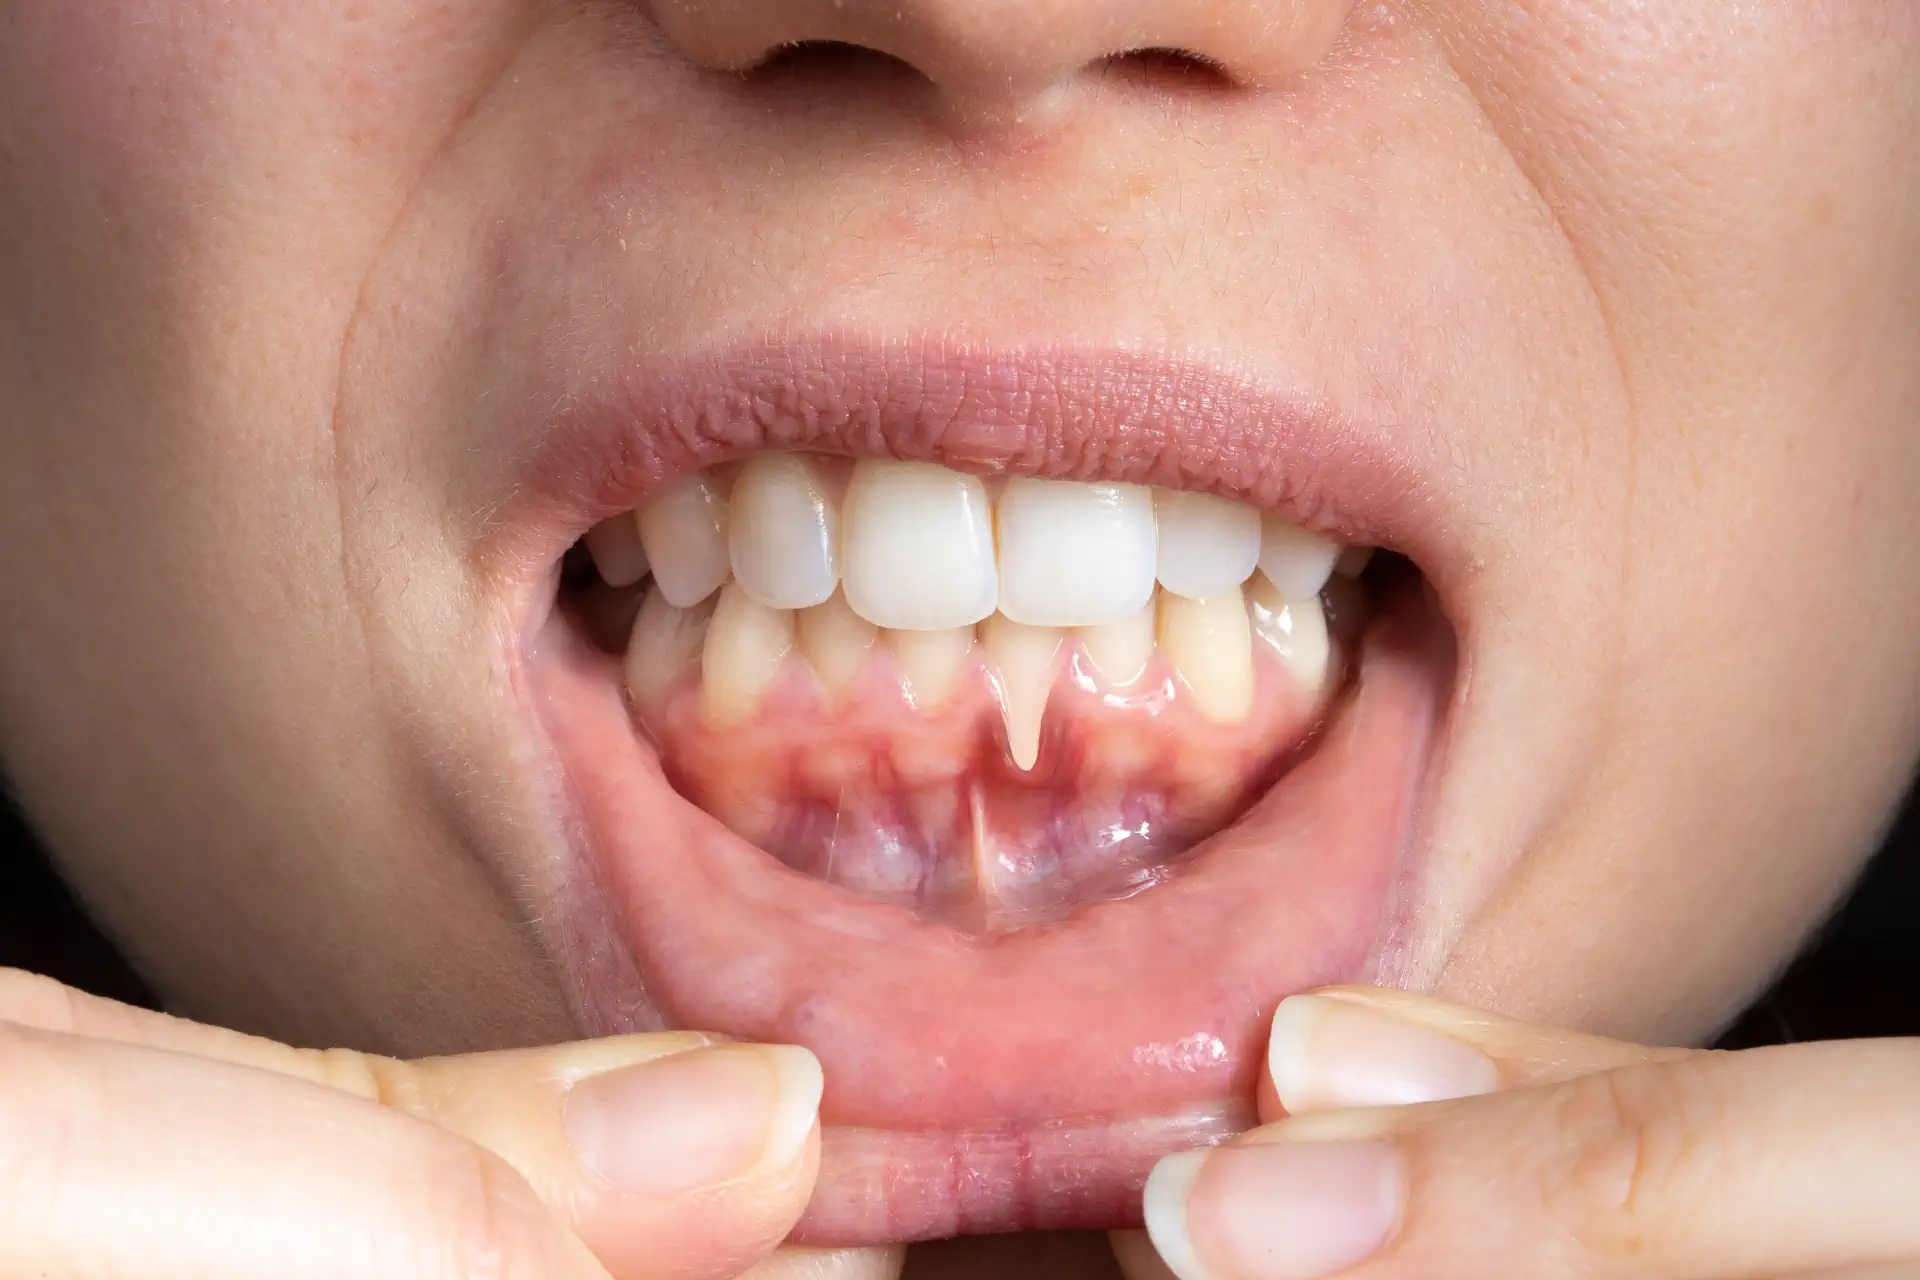

Typische Anzeichen sind freiliegende Zahnhälse, verlängerte Zahnkronen, schwarze Dreiecke zwischen den Zähnen und oft eine erhöhte Empfindlichkeit gegenüber Kälte oder Berührung. Auch Zahnfleischbluten kann begleitend auftreten.